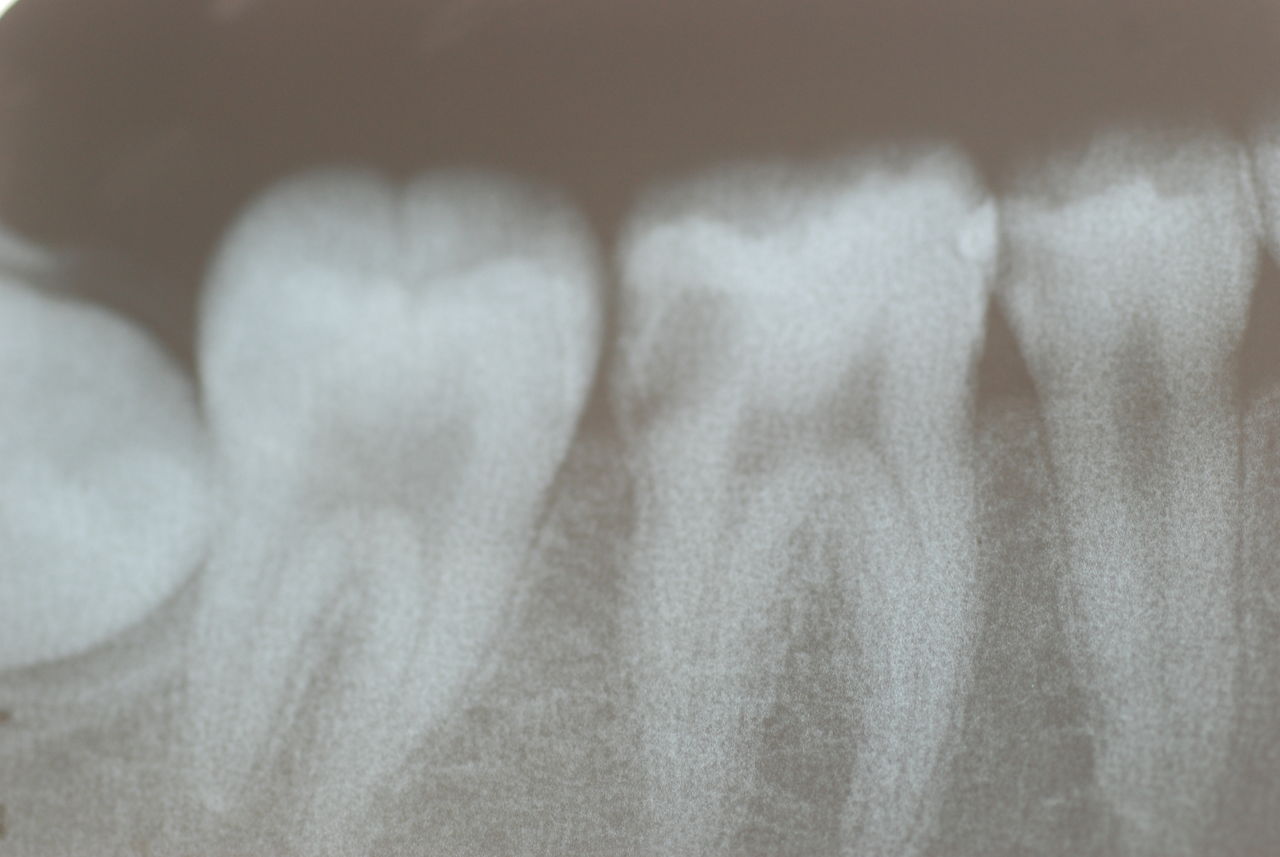

レントゲンでは小さいですが、こう言う虫歯が一番怖いのです。

治療の成功率は極めて悪くすぐ再発しやすいのです。

隣の14歳大臼歯がひどい虫歯になり治療不可能になりつつある状態のレントゲン